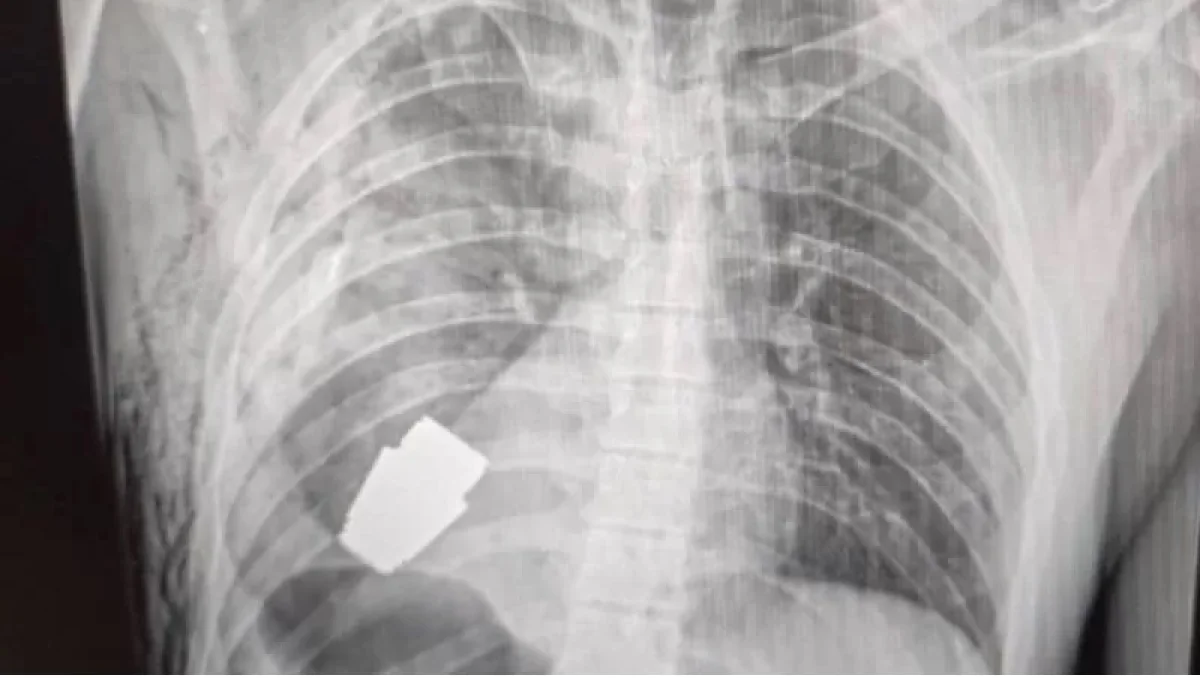

सैनिकाच्या छातीतून काढला न फुटलेला ग्रेनेड

युक्रेनमधील एका सैनिकाच्या छातीमधून न फुटलेलं ग्रेनेड काढण्यात आलं आहे.

युक्रेनच्या सैनिकी वैद्यकसेवेने फेसबूकवर त्याचा एक्सरे फोटो प्रसिद्ध केला आहे. या सैनिकाच्या हृदयाच्या अगदी जवळ हे ग्रेनेड असल्याचं दिसतं.

तसेच, त्याच्या छातीतून ग्रेनेड काढणाऱ्या डॉक्टरांचाही फोटो या फैसबूक पेजवर प्रसिद्ध करण्यात आला आहे.

या पोस्टमध्ये म्हटलं आहे, या शस्त्रक्रियेच्यावेळेस वैद्यक कर्मचाऱ्यांसाठी सैन्यातील 2 अभियंतेही उपस्थित होते. जखमी झालेल्या सैनिकाची तब्येत आता सुधारत असल्याचे यामध्ये लिहिले आहे.

हे ग्रेनेड शस्त्रक्रियेच्यावेळेस कधीही फुटलं असतं, म्हणून रक्त वाहणं थांबवण्यासाठी वापरली जाणारी इलेक्ट्रोकोगुलेशन उपचारपद्धतीही वापरली नाही असं या पोस्टमध्ये म्हटलं आहे.

हे ग्रेनेड त्या सैनिकाच्या छातीत कसं गेलं हे अद्याप समजलेलं नाही. पण ते VOG ग्रेनेड असल्याचं समजतंय. ते 4 सेंमी. आकाराचे असून त्याचा 400 मीटर अंतरापर्यंत मारा करता येतो.

ही शस्त्रक्रिया मेजर जनरल आंद्री वर्बा यांनी केली आहे. त्यांना युक्रेनच्या लष्करातले सर्वा अनुभवी शल्यचिकित्सक मानलं जातं.